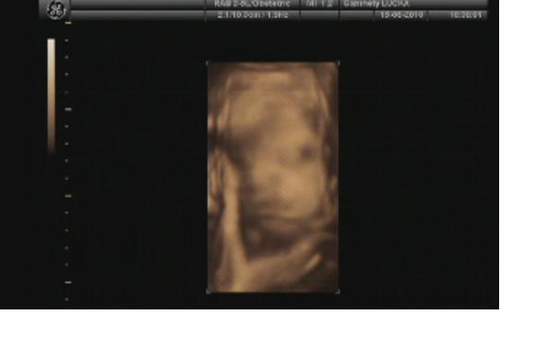

i gratulacje dla rodzicow!!!faktycznie sie synus wbil rowniutko w czasie ;-)